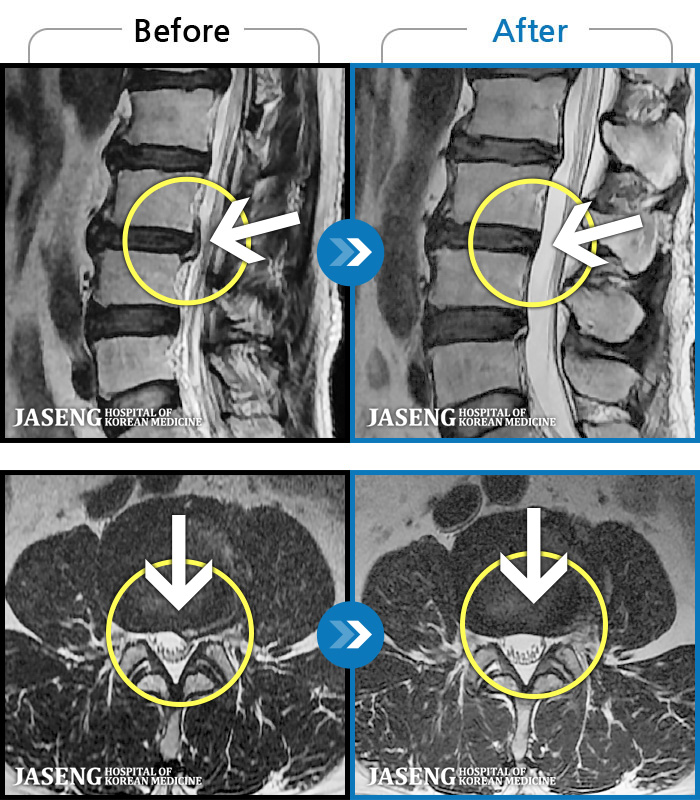

내일이면 퇴원이다. 3월부터 주위에서 허리통증 치료 잘 한다는 통증의학과ㆍ신경외과ㆍ정형외과 병원 3곳을 돌아다니며 허리 신경주사 12번 ,도수치료 10번, 물리치료 등등 정알 여러가지를 받았다. 그러나 치료와 처방 받은 진통제만으로는 일상생활을 하기가 많이 힘들었다. X레이 사진으로 확인한 척추 전방전위증은 결국은 수술을 받아야 한다고 하였다.

전방전위 대해 알아보다가 자생병원 홈페이지에서 김상돈 병원장님이 임상치료 하셨다는 것을 보고 잠시의 망설임도 없이 전화 예약하고 입원 하게 되었다.

MRI 검사로 정확한 진단을 시작으로 병원장님의 치료를 2주간 받았다. 친절한 설명과 따뜻한 배려로 정말 마음 편하게 치료 받을수 있었다.

극심한 통증으로 입원 첫날에 맞은 진통제 주사는 더 이상 필요없게 되었다 다시한번 김상돈 병원장님께 감사 드립니다.